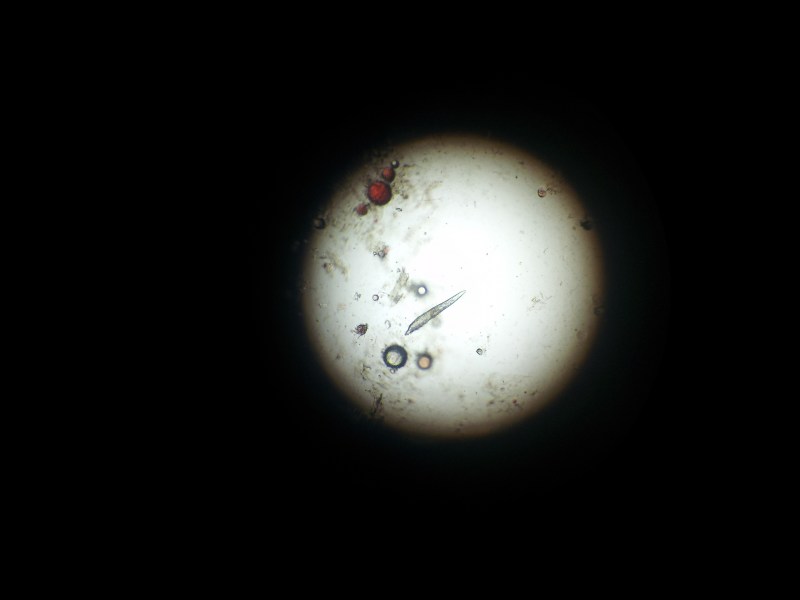

zdjęcie 2